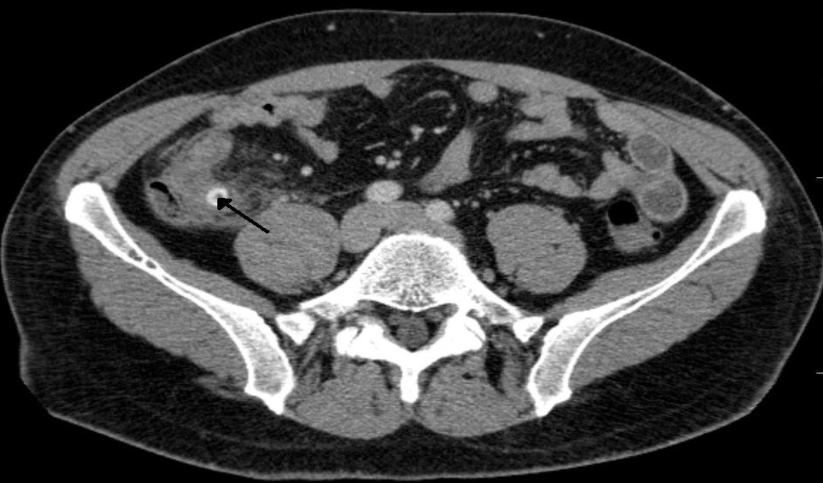

Axial CT of the abdomen after oral and IV contrast medium administration

A large, relatively sharply demarcated tumor can be

seen in the right kidney. This finding is characteristic of

Renal Cell carcinoma.